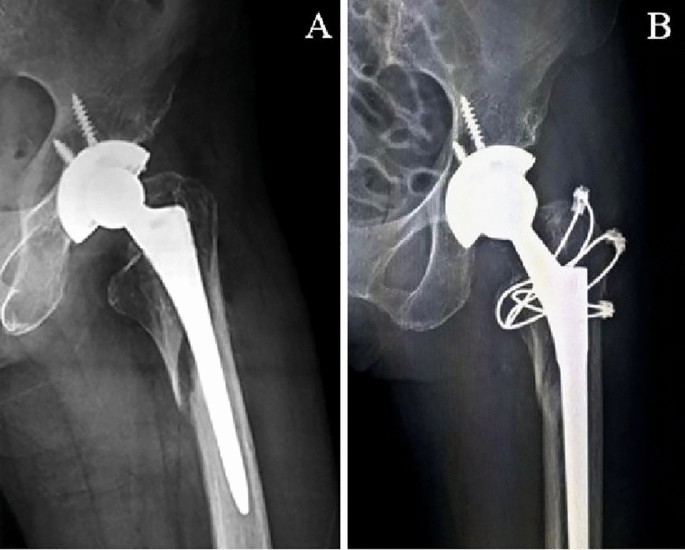

Two treatment methods were adopted. Longer stem revision and internal fixation (LSRIF) with cables was applied in 24 cases (Figs. 1 and 2). Open reduction and internal fixation (ORIF) with cables was done in four cases (Fig. 3). The choice of surgical treatment was based on the patient’s physical condition. The standard treatment was LSRIF, while ORIF was chosen if the patient was in poor condition and could not tolerate LSRIF.

Case 8, an 81-year-old woman. (A) Anterior–posterior radiograph after hemi-arthroplasty. (B) After a fall in the ward, the continuity of the left medial femoral cortex was disrupted on anterior–posterior and lateral radiographs. (C) Postoperative anterior–posterior radiograph shows the patient with a longer stem revision and internal fixation with cables.